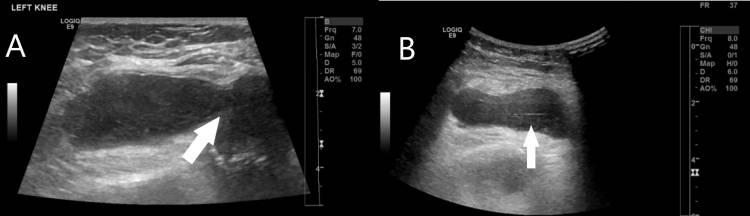

经检查,左膝触痛,有明显红斑和发热。患者只有0-90度的活动范围,运动疼痛。实验室评估显示,白细胞(WBC)计数正常,但炎症标志物较高。对左膝进行了X光检查(图1),结果显示关节周围软组织肿胀,髌上脂肪垫膨隆,指向关节积液。超声(US)还发现膝关节周围软组织肿胀,髌上囊扩张,滑膜增厚,液体少(图2)。

图2 左膝超声显示不同的切面(A和B),箭头指向关节周围软组织肿胀。髌上囊扩张(B中箭头)明显。膝关节滑膜增厚,液体极少(A中的箭头)